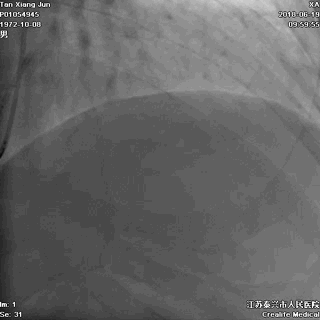

我们曾接诊过一个姓戴的老奶奶,79岁,她出现胸痛后,先是自己在家观察和处理,过了9小时还没缓解,才赶往医院。我们马上进行了急诊手术,很成功,命是保住了,但因为太迟来就诊,心脏功能已经严重受损。

术后,她反复出现心衰,生活质量明显下降。

血管闭塞

血管开通

记住:时间就是心肌,时间就是生命。每耽误一分钟,就意味着更多心肌细胞坏死。